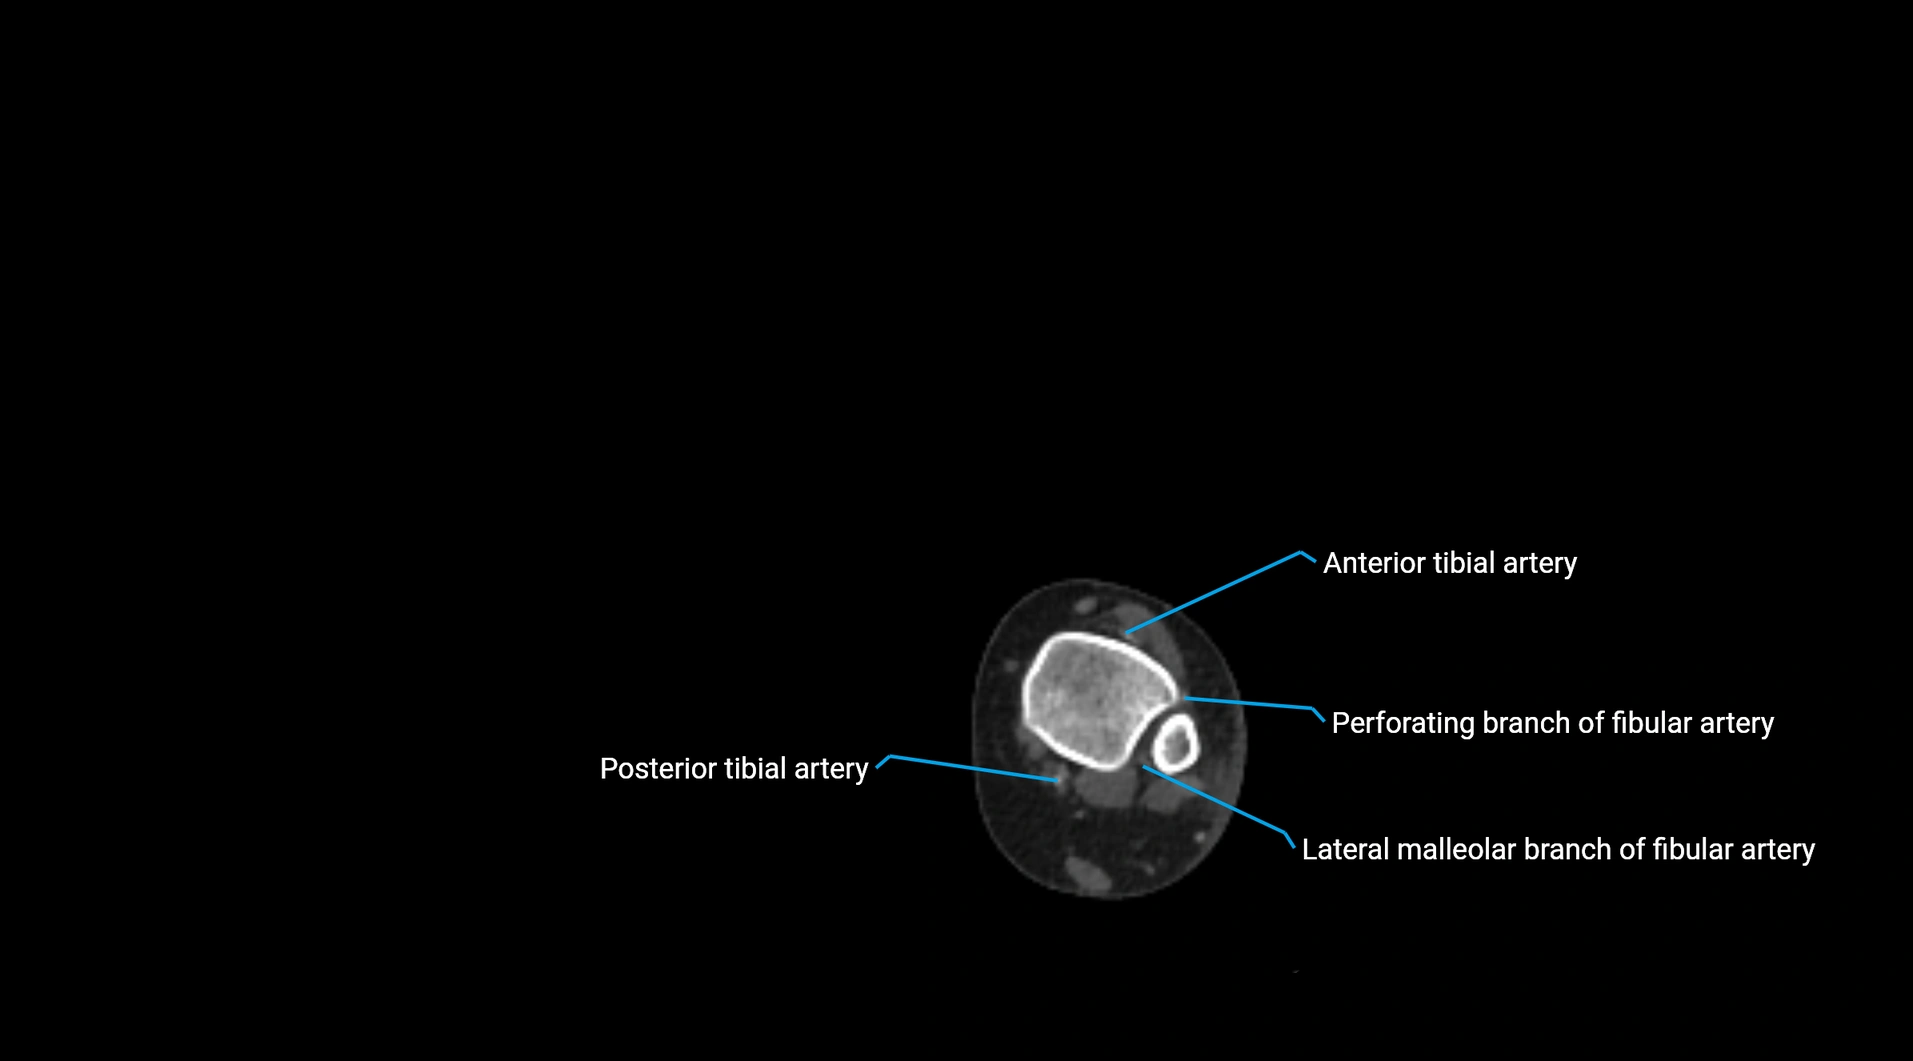

CT images

image